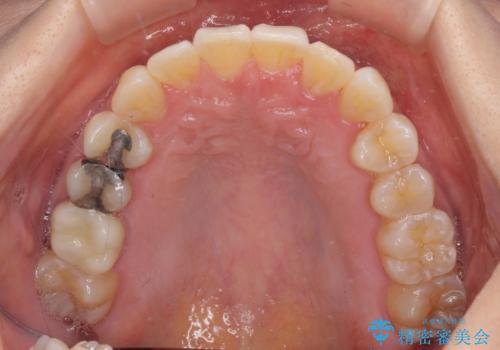

前歯のクロスバイト インビザライン矯正で改善

- むし歯治療を契機に、長年気にしていた前歯のクロスバイトの改善を希望された患者様です。

汚れが溜まりやすく、歯ぎしりがうまくできないため、インビザラインを用いて矯正治療を行うこととしました。

インビザラインによる前歯のクロスバイトの改善は、治療期間中に前歯でしか咬めない時期が続いたり、歯肉退縮や歯髄壊死のリスクが高まったりと、治療中にトラブルを抱えることがあります。

特に上顎側切歯(真ん中から2番目の歯)が舌側に引っ込んでいるケースは、インビザラインでは改善しきれないことがあると言われています。